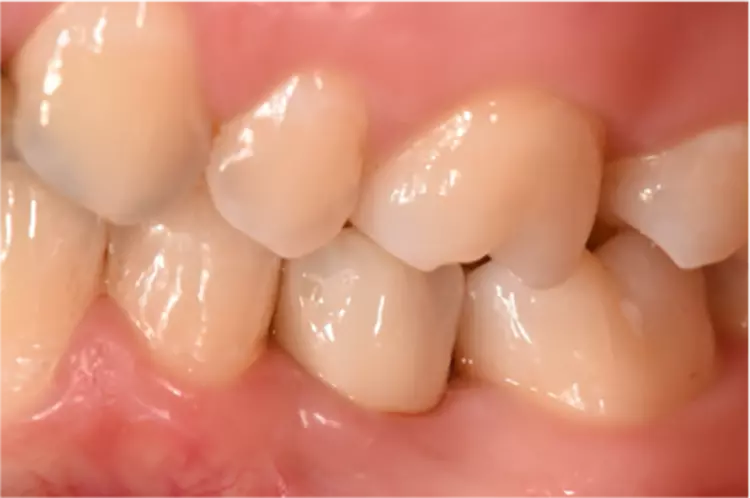

Die Implantate wurden im üblichen chirurgischen Vorgehen inseriert und sofort mit einem Provisorium aus Polymethylmethacrylat (CAD-Temp, VITA) versorgt, wobei die Provisorien außer Okklusion geschliffen wurden und darauf geachtet wurde, dass approximal nur sehr schwache Kontakte bestanden (Abb. 3a bis e). Die definitive prothetische Versorgung erfolgte im Unterkiefer nach frühestens 2 Monaten, im Oberkiefer nach frühestens 4 Monaten. Die Restaurationen wurden aus verblendetem Zirkonoxid hergestellt (VITA YZ HT / VITA VM 9, VITA).